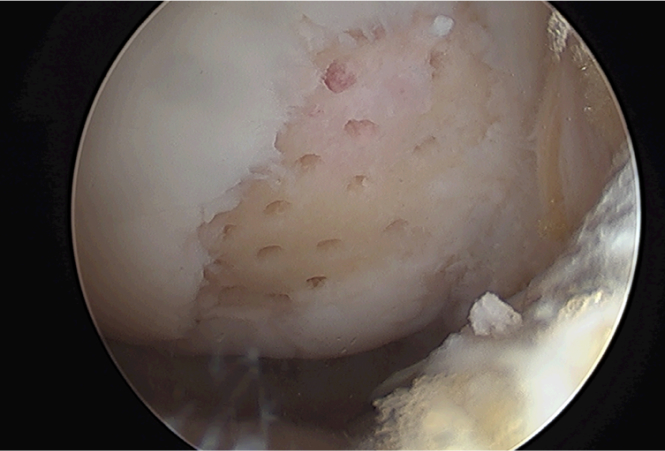

수술전

수술후

미세천공술 전

미세천공술 후